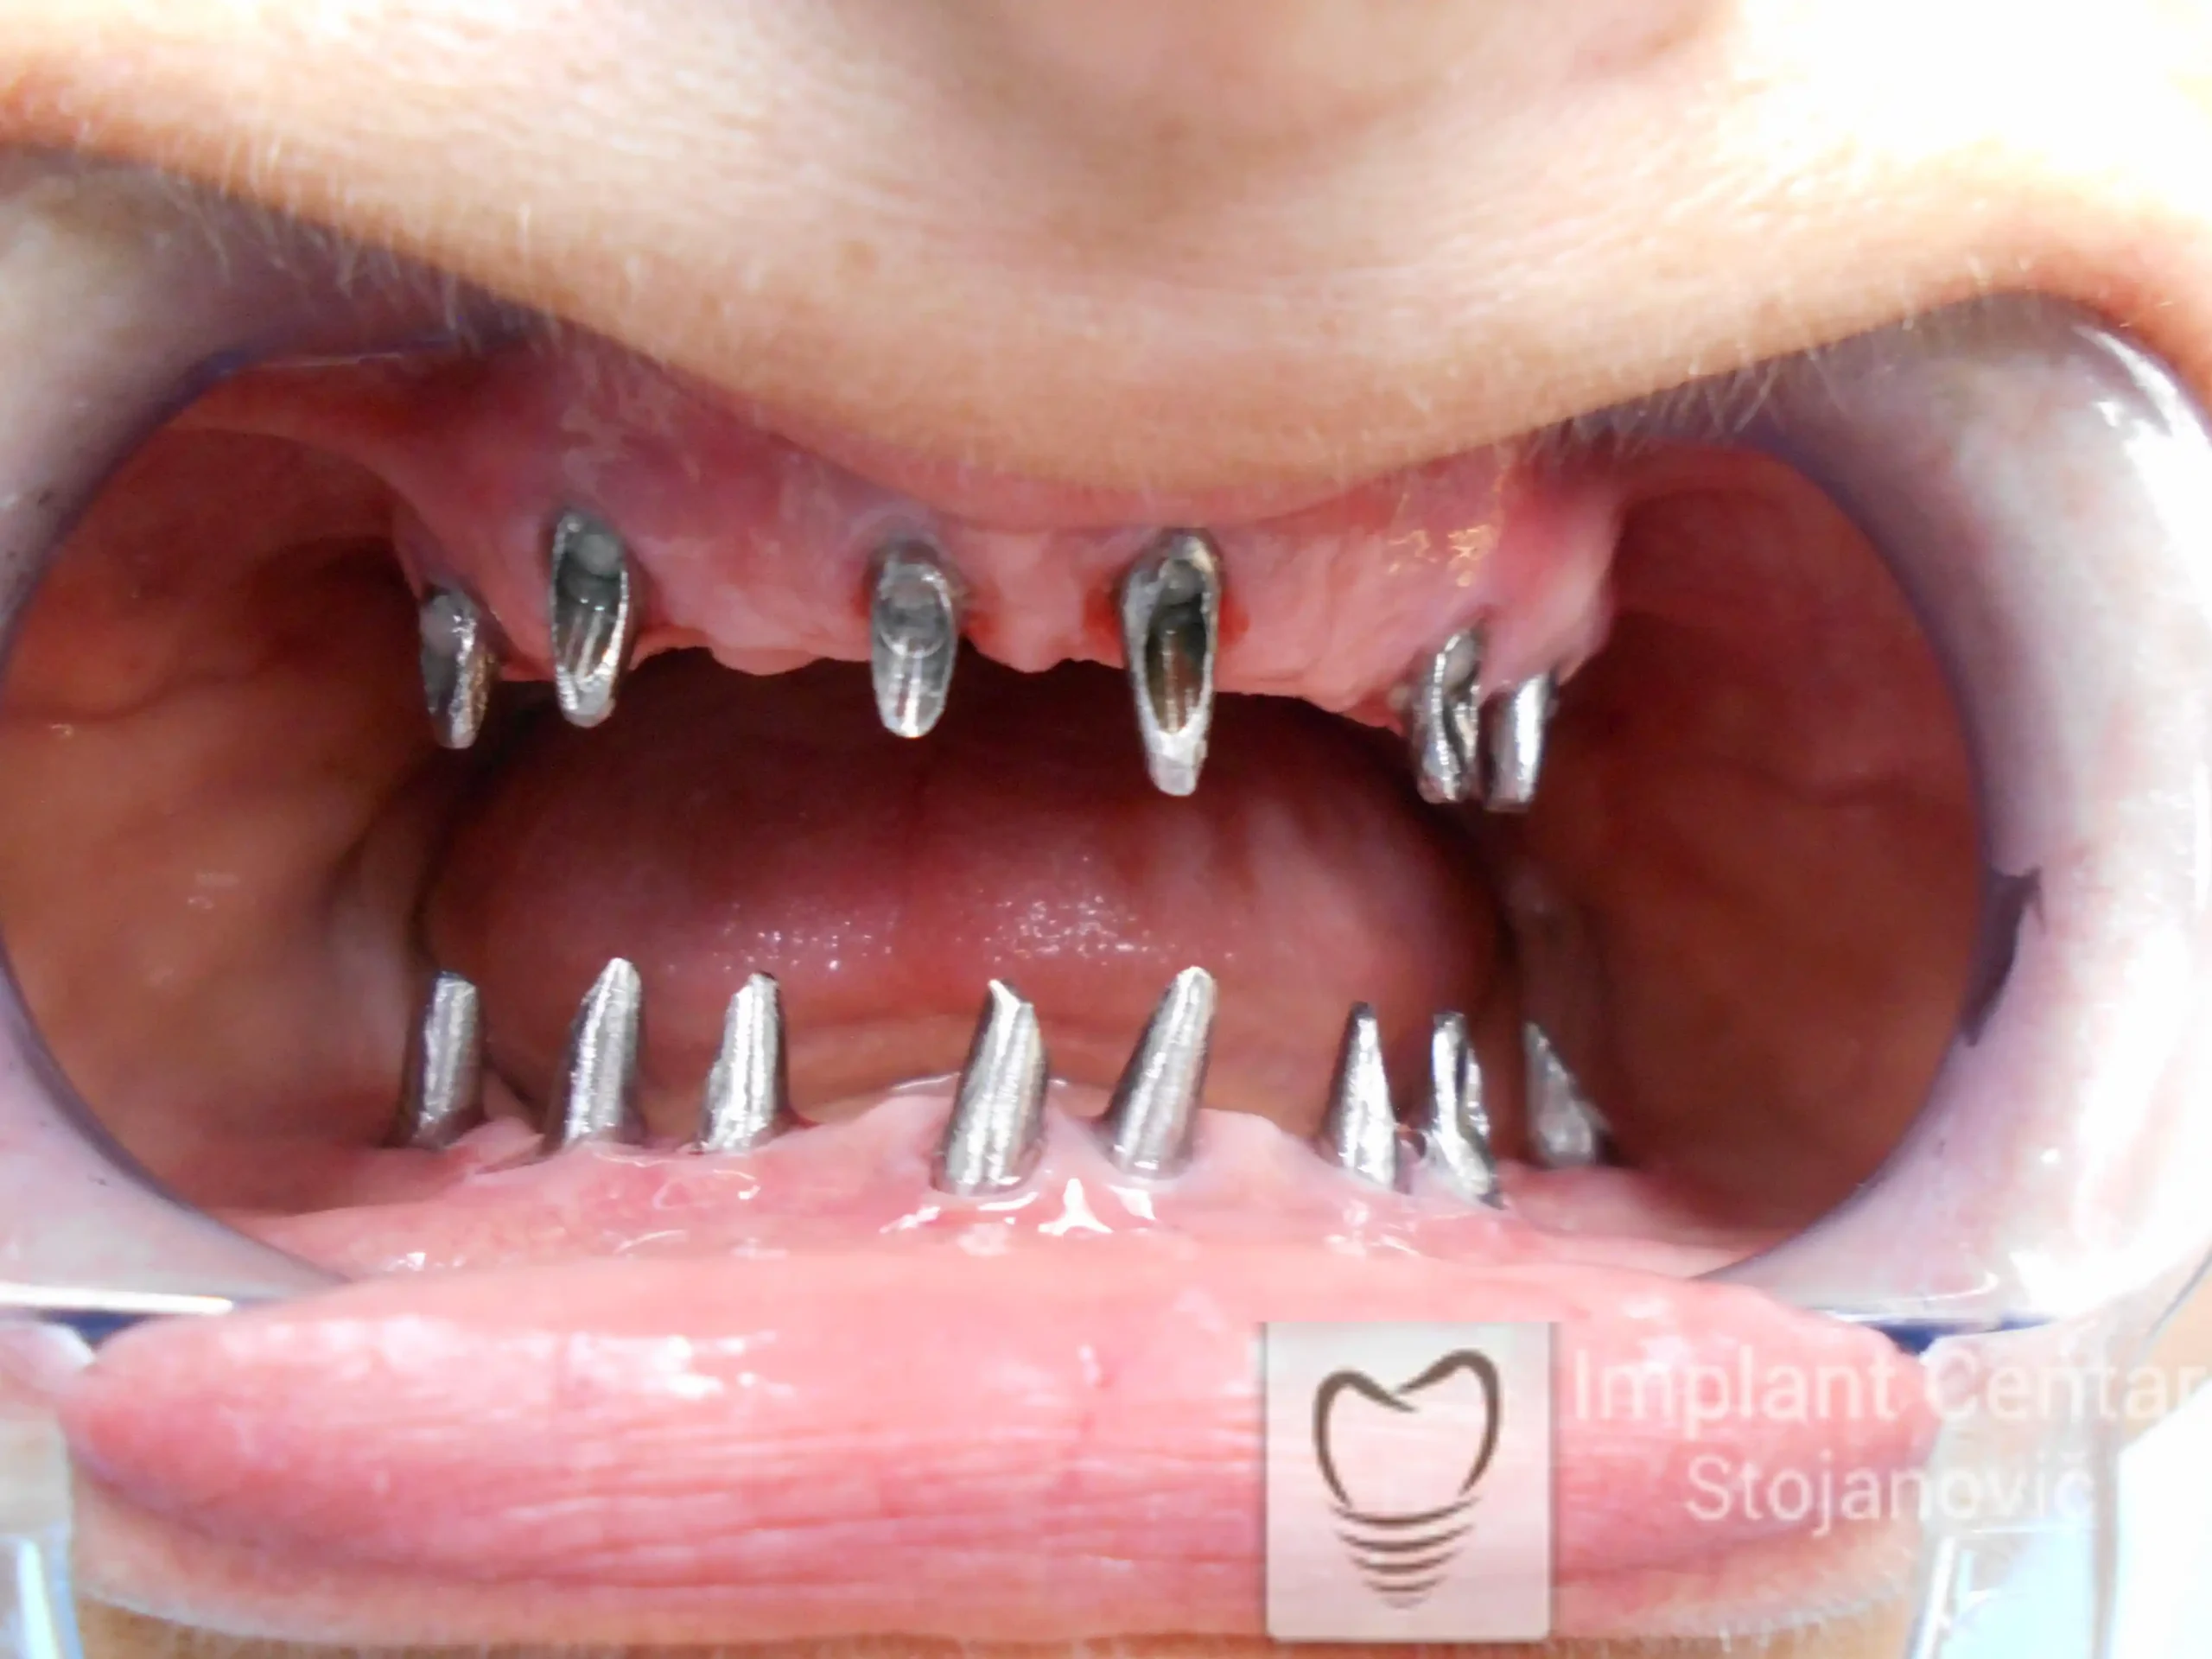

Nakon vađenja zuba, ugrađeni su implantati. Na slici 3 prikazan je ortopan snimak sa ugrđenim implantatima. Tokom perioda osteointegracije, pacijent je bio zbrinut fiksnim privremenim krunicama na implantatima, koje su izrađene samo dva dana nakon hirurške intervencije.

Na slikama 5. i 6. prikazan je izgled definitivnih cirkonijum-keramičkih mostova na implantatima.